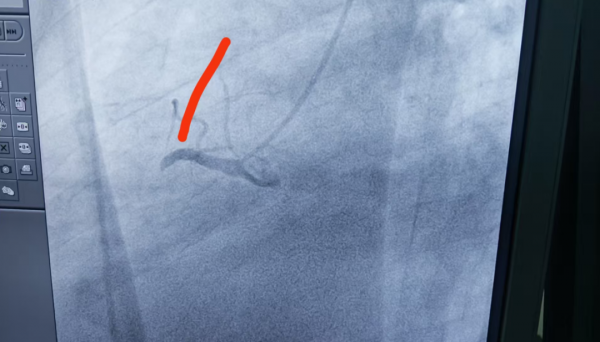

1、39岁男性,前降支闭塞,行血栓抽吸+冠脉内溶栓。

2、71岁男性,右冠闭塞,行药物球囊扩张成形术。

3、69岁男性,双支病变,行介入治疗。